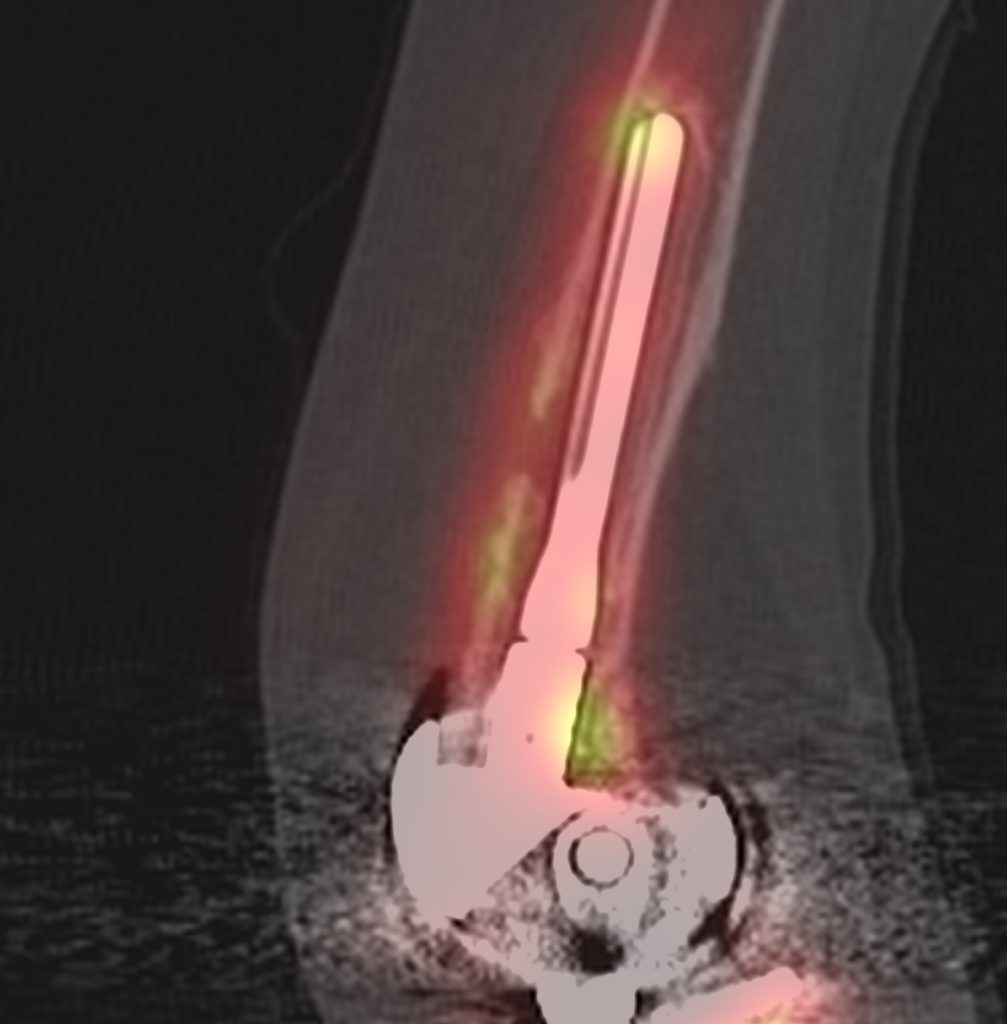

The tibial component is loose when there is focal increased tracer uptake at the sites of maximal mechanical stress; usually at the tip of the tibial component and at the contralateral tibial tray. Loosening of the femoral component is often associated with increased uptake adjacent to the posterior aspects of the condyles, adjacent to the bone prosthesis interface. The CT component will show a periprosthetic lucency that is greater than 2mm in width, with irregular margins, at the site of increased bone uptake.

Infected prostheses usually have increased activity in dynamic and blood pool phases throughout the bone surrounding the infected prosthesis. On SPECT-CT there is diffuse increased uptake around the bone prosthesis interface, with periosteal reaction, soft tissue oedema, soft tissue abscesses or joint effusions.

The incidence of total knee replacement periprosthetic fractures is low and has been reported as 0.3 - 5.5%.

Periprosthetic fractures can cause pain following surgery, lead to aseptic loosening, non-union, failure of osteosynthesis, infection, wound healing disorders and re-fractures. Bone scans can identify periprosthetic fractures, as increased bone turn-over associated with osteoblastic activation. However, SPECT-CT allows more accurate localisation of the fracture, along with providing information on prosthesis stability. One should look for cross-bridging of new cortical bone and new trabeculation of cancellous bone, which can be seen on CT. Increased bone uptake on SPECT indicates viability of the fractured component.